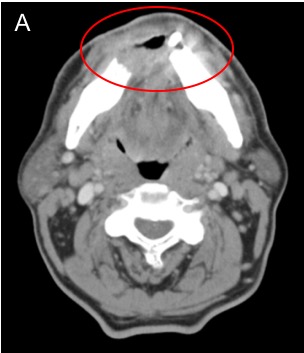

To better evaluate the extent of the primary lesion, its proximity to critical structures such as major vessels, and to assess for lymphadenopathy not appreciable on physical exam, computed tomography (CT) scan of the head and neck with contrast is commonly ordered as part of the initial workup. Compared to other imaging modalities, CT is especially sensitive for detecting osseous involvement, particularly cortical erosions of the mandible and maxilla [40]. Significant bone involvement in oral cancer affects staging and surgical planning. Figure 4 shows CT images of a FOM SCC with tumor enhancement and cortical erosion of the mandible.

Figure 4. Computed Tomography (CT) of Oral Cavity Squamous Cell Carcinoma (SCC). [A] Axial CT head with contrast demonstrates an ill-defined enhancing mass involving the anterior floor of mouth. [B] Axial CT head windowed for bone shows osseous erosion through the cortex of the mandible from alveolar SCC.